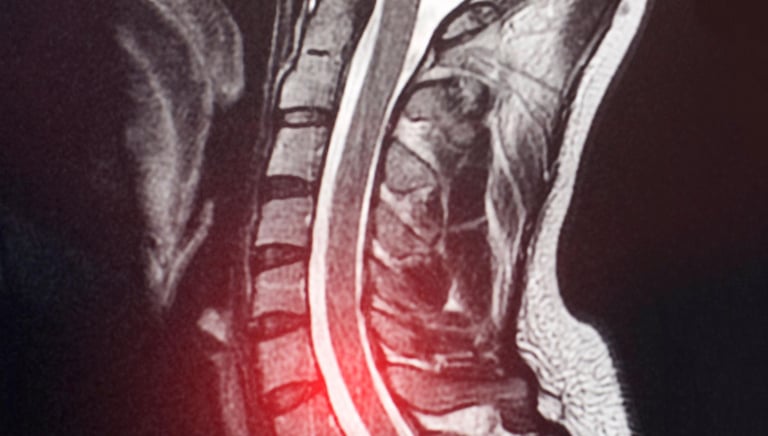

MRI shows unclear or suspicious lesions

MRI shows abnormal lesion

MRI or CT scan reports